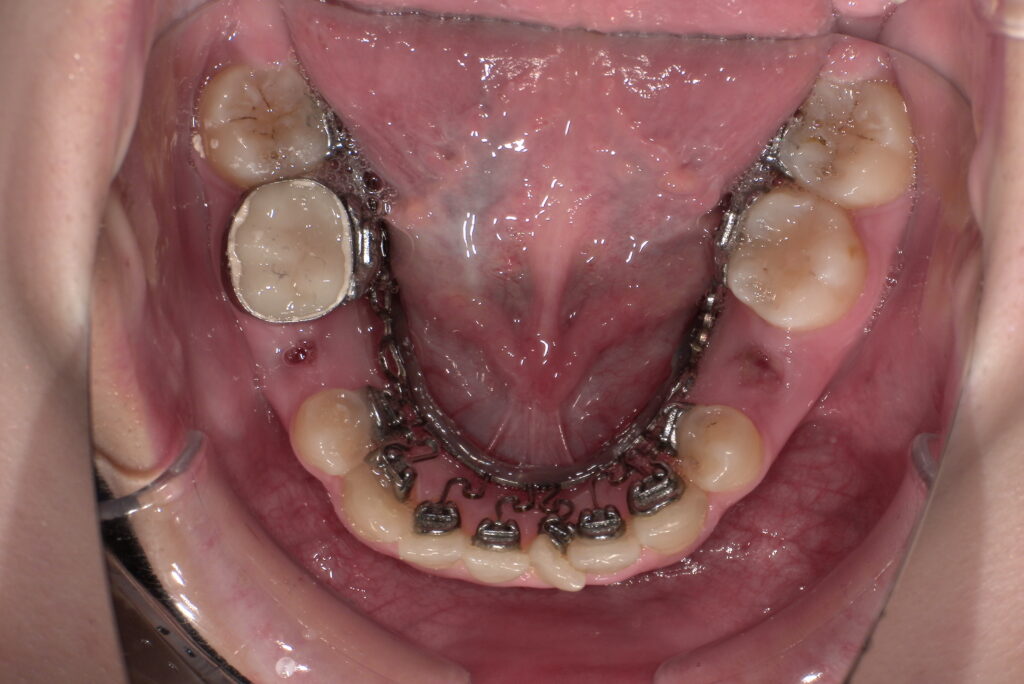

📸治療経過写真

当院で裏側矯正治療しているスタッフの経過写真をご参考にしてください。

上下左右小臼歯を1本ずつ計4本抜歯して現在も治療中です。「歯を抜いた隙間が閉じた量」、「前歯の移動量」、「正面から見た前歯の位置」に注目して見てもらえると、歯の移動の早さが目に見えて分かるかと思います。

約4か月後

下顎